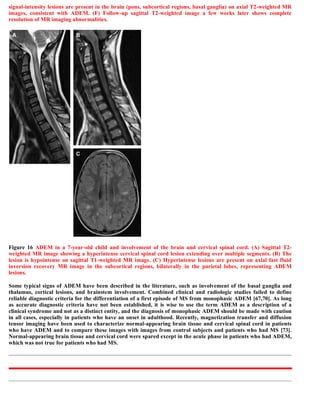

This document discusses a case of spinal multiple sclerosis in a 40-year-old patient. MRI images show well-defined pencil-shaped lesions occupying 2-3 spinal segments that are hypointense on T1-weighted images and hyperintense on T2-weighted images. Diffuse abnormalities are also seen as poorly demarcated hyperintense regions on T2-weighted images. The diagnosis is spinal multiple sclerosis. The document then discusses features of spinal MS lesions seen on MRI such as focal lesions, diffuse abnormalities, and spinal cord atrophy, and compares features of MS to other conditions like neuromyelitis optica.